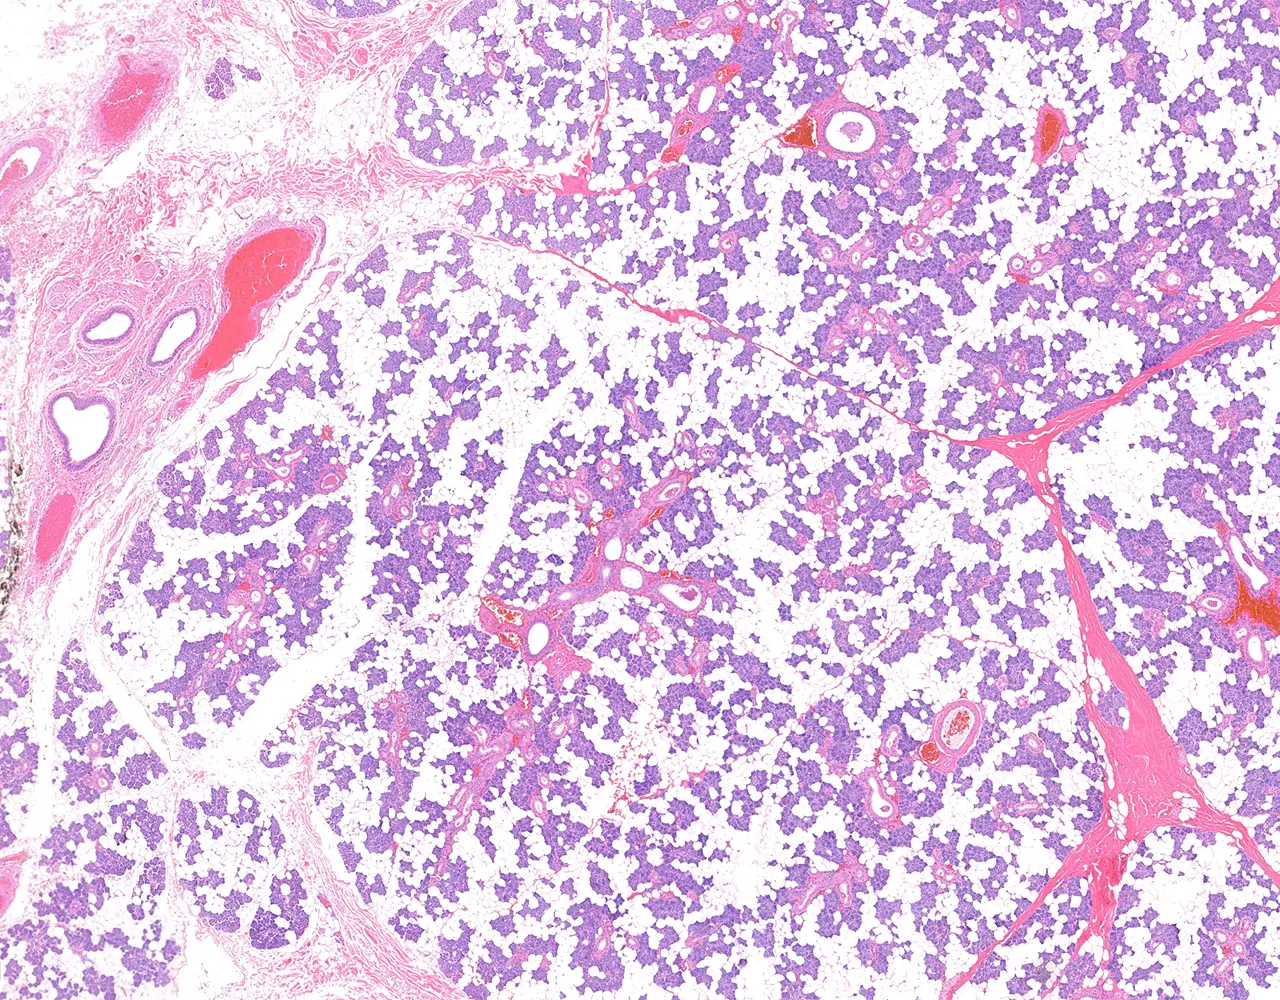

- The major salivary glands are paired organs and include the parotid, submandibular, and sublingual glands.

- They are compound tubuloacinar exocrine glands.

- Each gland is surrounded by a thin capsule.

- The capsule extends septa into the glandular parenchyma, dividing it into lobes and lobules.

- Microscopically, the functional structure of a salivary gland consists of secretory acini and a duct system.